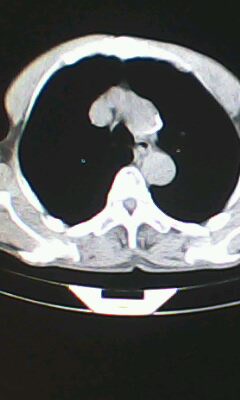

标题: CT26182:男 胸憋 无其它异常症状

胸廓呈桶状,双膈低平,肺实质及纵隔未见明显异常密度灶考虑肺气肿.

肺气肿

以下是引用ctkz987在2010-5-5 21:30:00的发言:[br]胸廓呈桶状,双膈低平,肺实质及纵隔未见明显异常密度灶考虑肺气肿.

临床诊断:copd

慢阻肺是临床诊断,未见明显异常。